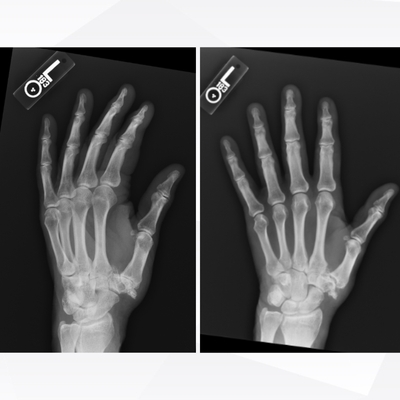

Click on an image below to view more info.